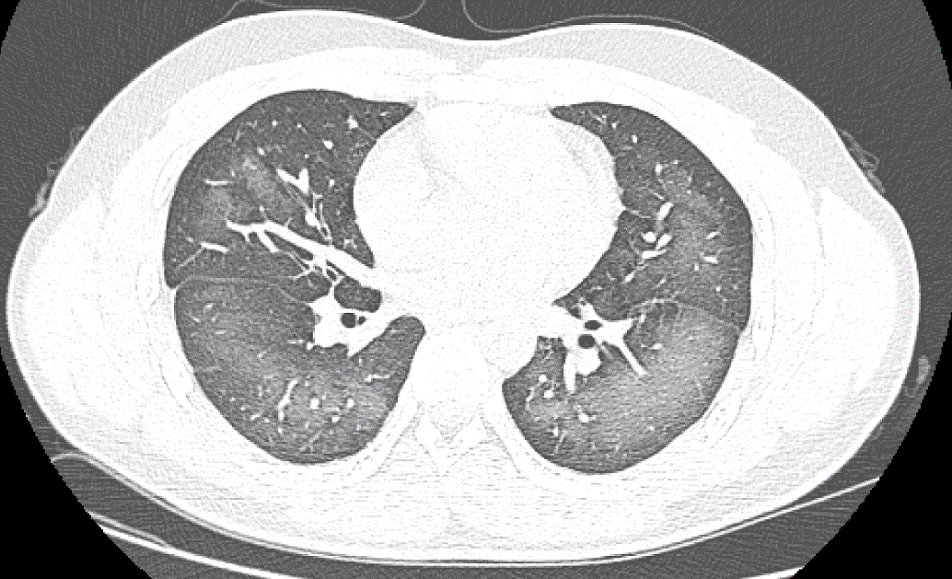

卻在使用后會出現“白肺”

原來,小伙李林(化名)外出前使用了防曬噴霧,在對著面部噴灑時一不小心誤吸,隨即出現胸悶、咳嗽的癥狀。癥狀一直持續到第二天仍未好轉。經檢查,因吸入噴霧,導致李林雙肺赫然呈現大范圍白色樣病變,報告提示“白肺”。關于噴霧式防曬霜